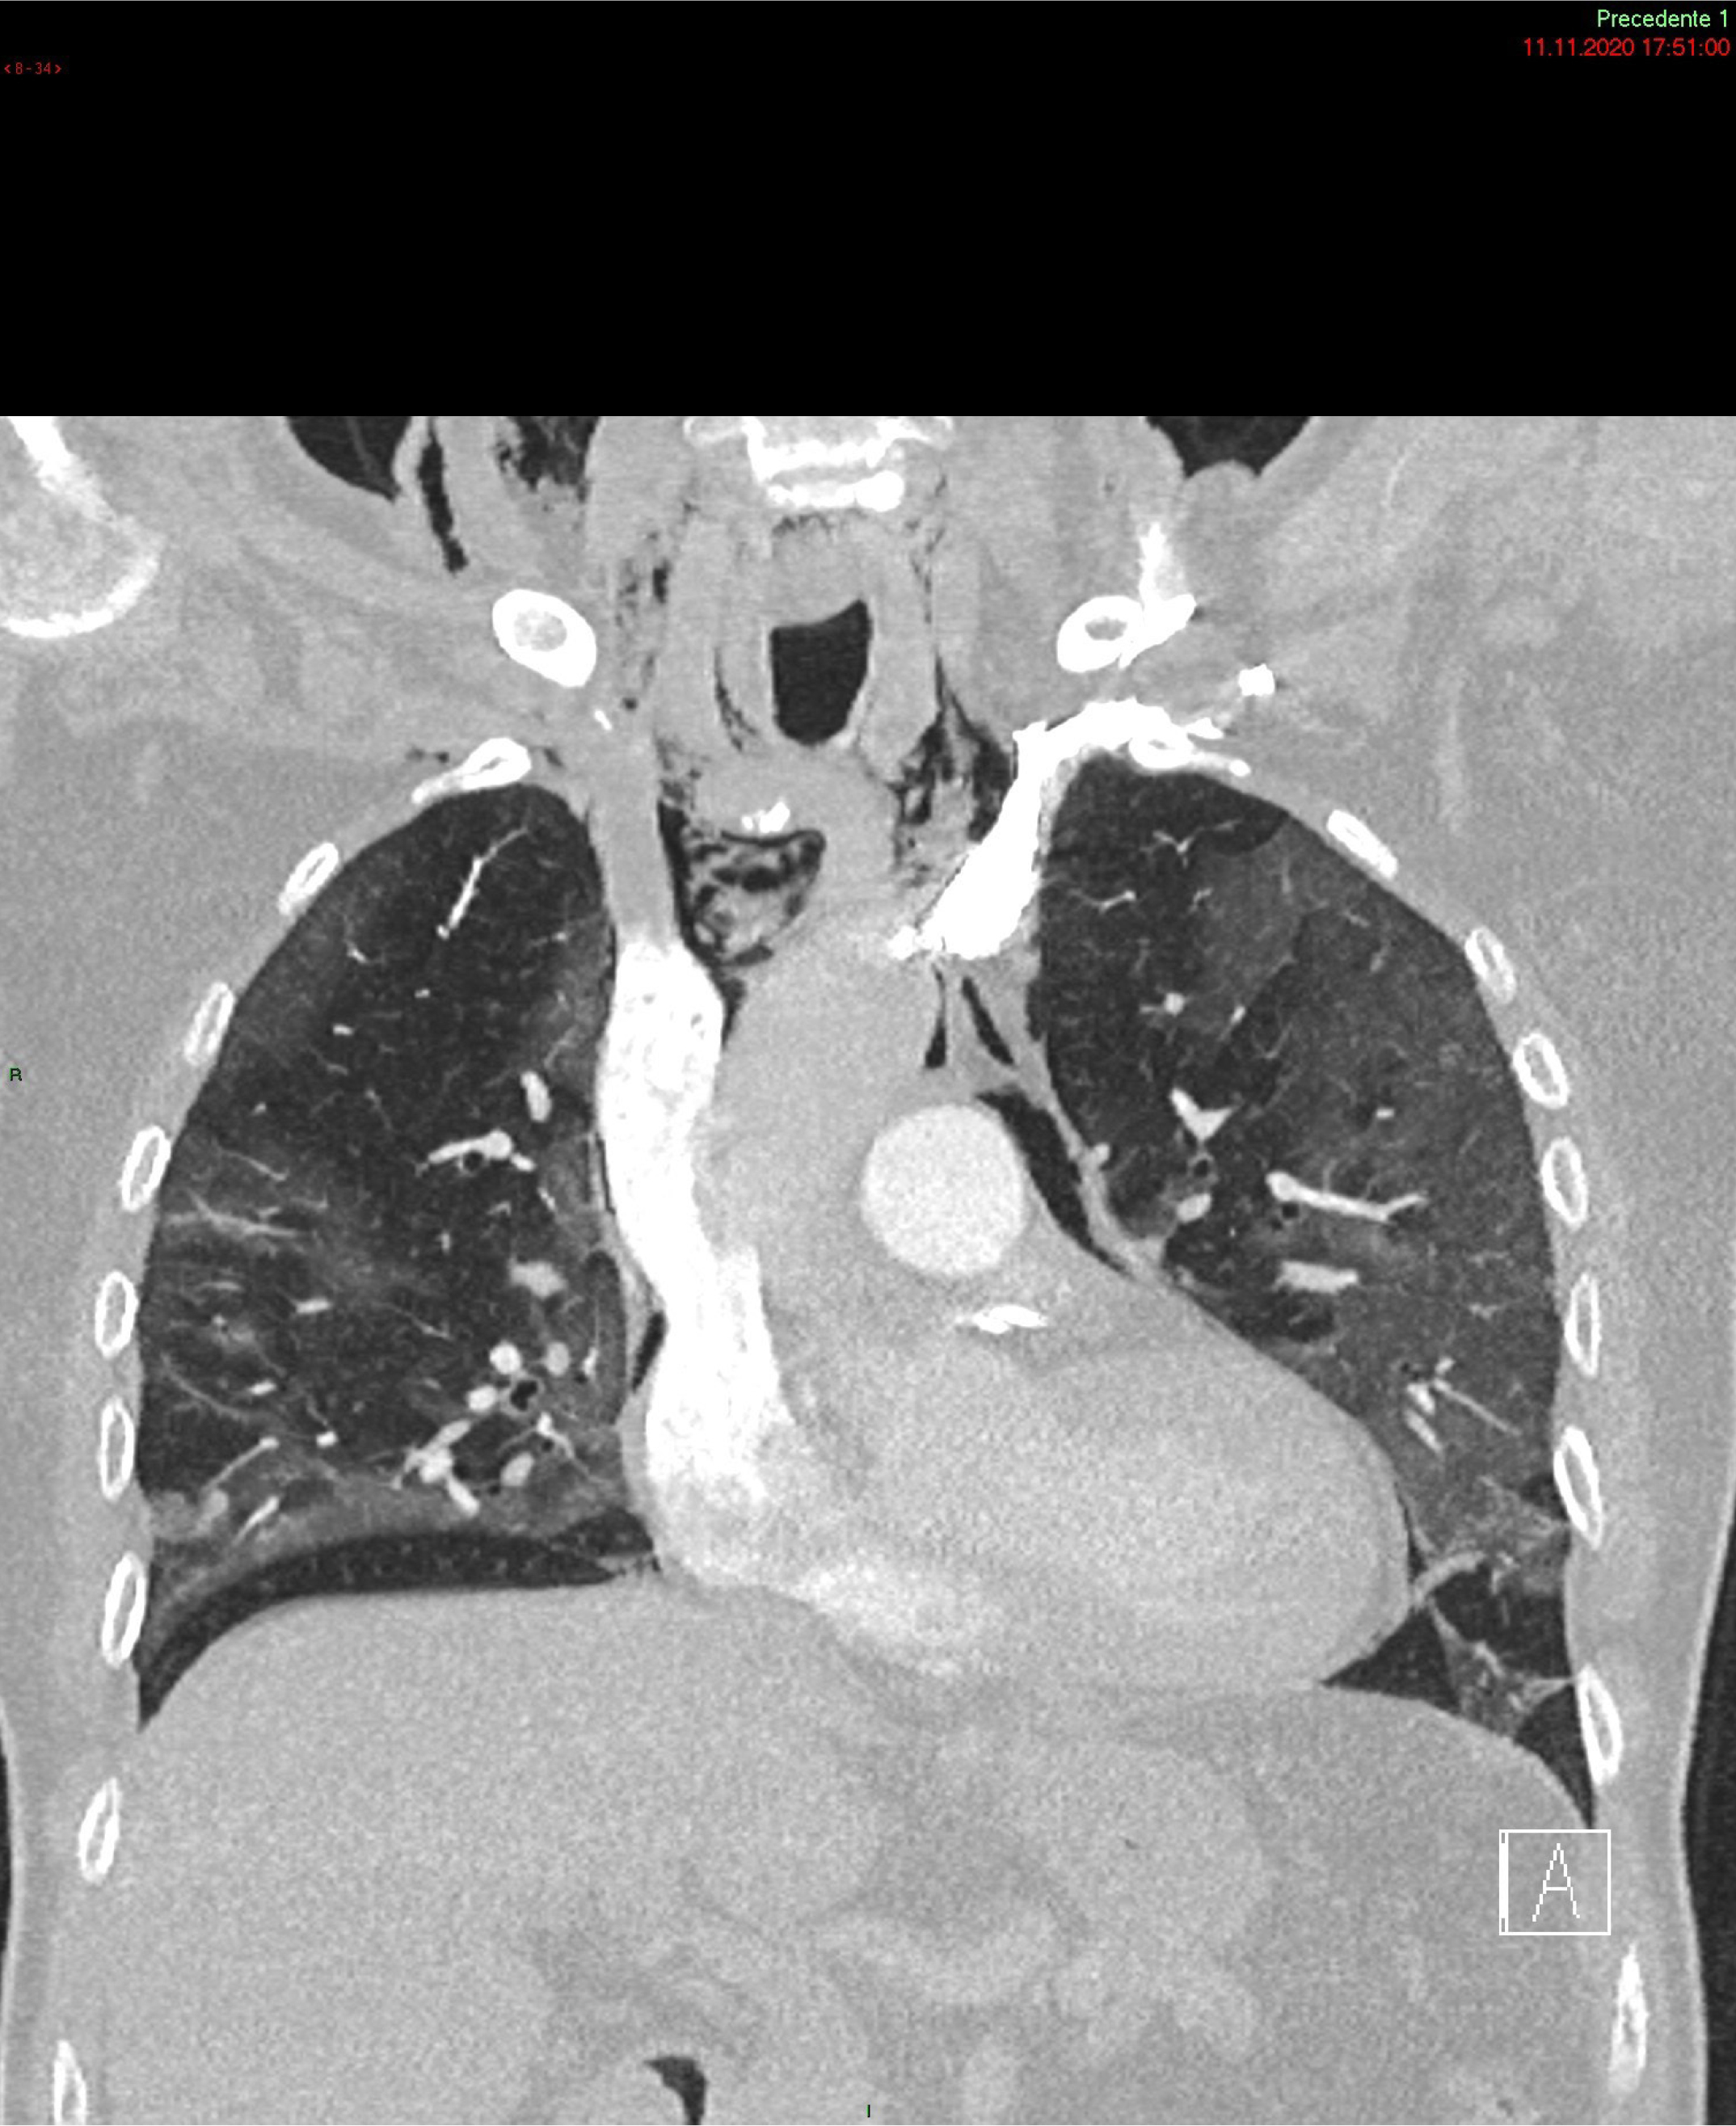

Figure 2: Chest computed tomography scan: air leakage and dissection along bronchovascular sheaths with pulmonary interstitial emphysema and pneumomediastinum, widely extending along the muscle bundles of the chest and neck causing subcutaneous emphysema.

SP and Subcutaneous Emphysema (SE) have been reported as uncommon clinical findings in patient with SARS- CoV-2 infection (Figure). Case series of patients with COVID-19 pneumonia and SP not on MV [9] showed that the SP was more likely to develop on 13th – 17th day since the onset of symptoms [9]. The most common associated conditions reported were older age, obesity and dyslipidemia, hypertension, diabetes mellitus, renal disease and asthma. Its occurrence is believed to be related to an increased pressure in the interstitial space, which may favor alveolar rupture hence resulting in pneumomediastinum [1012]. Therefore, invasive MV as well as coughing, emesis, a strong Valsalva maneuver or asthma exacerbation are considered possible triggering events [1,9,13,14]. Additional predisposing factors are high-dose corticosteroid therapy and anatomical anomalies [1,4, 9].